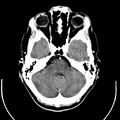

ويستعمل الأطباء فحوص التصوير المقطعي الحاسوبي لتشخيص كثير من الحالات مثل الأورام والإصابات وتجلطات الدم وكسور العظام. ويساعد التصوير المقطعي الحاسوبي أيضًا في معالجة بعض الأمراض، التي قد تتطلب جراحة بطريقة أخرى. فمثلا،ً يمكن للأطباء استعمال التصوير المقطعي الحاسوبي لإرشادهم إلى إدخال القثطار (أنبوب رفيع) إلى خُرّآج في الجسم لسحب الصديد من المنطقة الملوثّة.

يمكن للأطباء أن ينظروا داخل جسم المريض عن طريق طلب إجراء مسح للعظام والأوعية الدموية والأدمغة والأنسجة الرخوة بفضل ماسح التصوير المقطعي الحاسوبي (CT). بعد إجراء أول فحص طبي بالأشعة المقطعية للمريض في عام 1971، استخدم أطباء الأشعة عمليات المسح لتشخيص الأورام والصدمات والتخطيط للعلاج الطبي والجراحي والإشعاعي في جميع أجزاء جسم الإنسان تقريباً.

يستخدم التصوير المقطعي المحوسب في تشخيص الأورام الخبيثة والحميدة في مناطق مختلفة في الجسم.